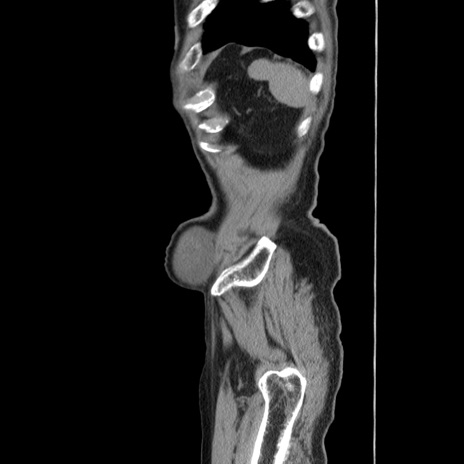

症例24(矢状断像)

【症例】80歳代男性

【主訴】左側腹部痛、嘔吐

【現病歴】本日早朝より左腹部に痛みあり。昼頃嘔吐認めたため、救急要請。

【既往歴】直腸癌(Mile手術)、胆摘

【身体所見】意識清明、BT 35.9℃、BP 221/93mmHg、SpO2 97%(RA) 、腹部:左ストーマ周囲に限局性の腹部膨隆あり。 膨隆部自発痛・圧痛あり・軟。